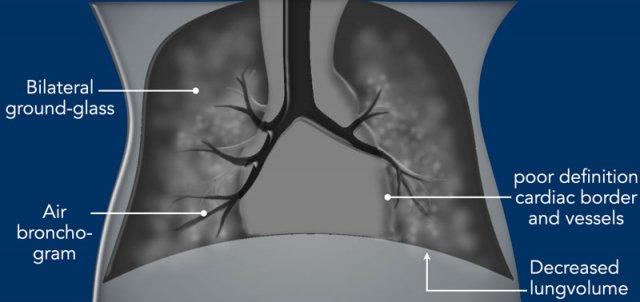

Imaging

- Giảm thể tích phổi trên phim X-quang ngực trừ khi bệnh nhân đang thở máy.

- Bilateral symmetric ground glass opacities.

- Air bronchograms can be visible into the periphery.

- Bờ tim và mạch máu phổi kém rõ nét, do nhu mô phổi kém thông khí.

- Thường không có tràn dịch màng phổi. Hình ảnh X-quang có thể không đối xứng ngay sau liệu pháp surfactant xâm lấn tối thiểu (MIST) và có thể giống với các bệnh lý khác như viêm phổi sơ sinh.